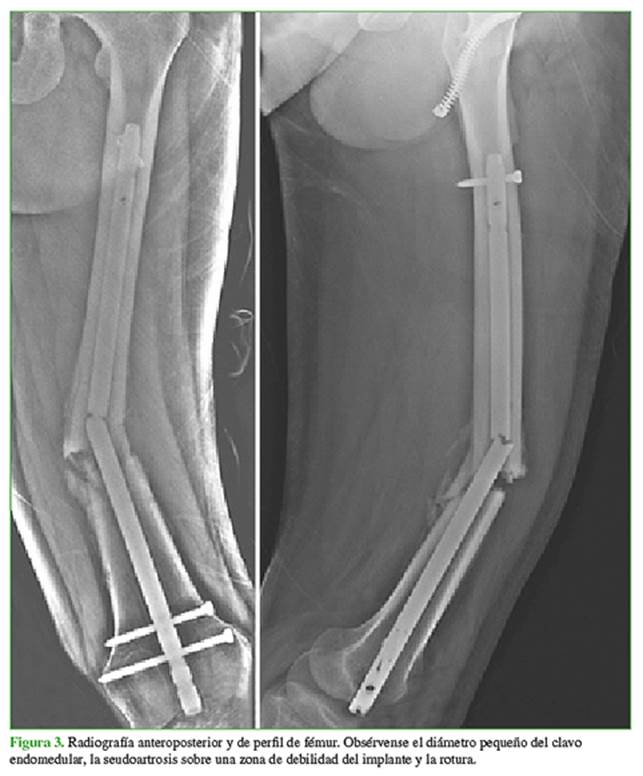

Al cuarto mes de la cirugía, el paciente refirió un aumento súbito del dolor en el miembro operado, durante la marcha, sin un traumatismo previo. En el control radiográfico, se observó la seudoartrosis y la rotura del implante. Se identificaron una serie de condiciones que combinadas llevaron al fracaso de la osteosíntesis. En primer lugar, la elección de un clavo endomedular de menor diámetro debido al antecedente de traumatismo de tórax. Segundo, el error de diseño del material de osteosíntesis, que presentaba un orificio de bloqueo en el tercio medio, sumado a esto, la proximidad del foco de fractura a la zona de debilidad del material de osteosíntesis.

Estas fueron las condiciones determinantes para la seudoartrosis, la fatiga del material y la rotura del implante (Figura 3).